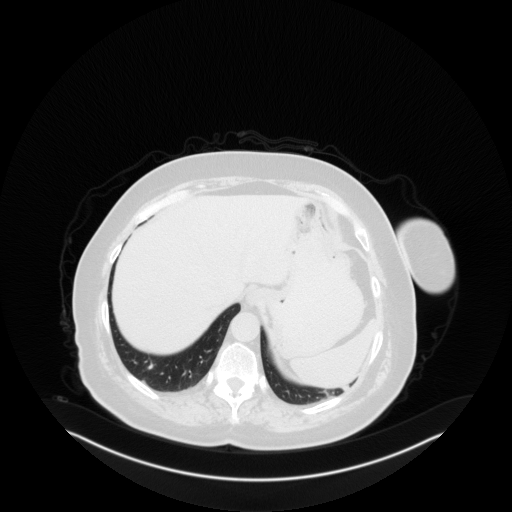

Image Grid

4Γ—3 grid: Rows show different image types (Original NATIVE, Reconstructed NATIVE, Original VENOUS, Generated VENOUS), Columns show windowing techniques (No Window, Lung Window, Mediastinum Window)

Original NATIVE CT scan (input)

Full window (WL 1023.5, WW 4095 β†’ Low βˆ’1024, High +3071)